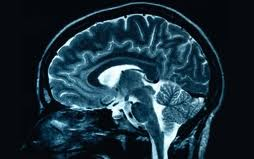

Erőszakos gyilkosságot, rablást elkövető bűnözők agyának vizsgálata során Gerhard Roth német neurológus azt találta, hogy az agyuk közepén létezik egy 'sötét folt', amit ő a gonoszság kiváltó okának tart, s ami az erőszakos viselkedés genetikai forrása lehet - számol be a Fox News.

A University of Bremen professzora bűnözök agyi vizsgálatát végezte el annak érdekében, hogy megnézze, van-e olyan genetikai ok, ami miatt valaki hajlamosabb erőszakos cselekmények elkövetésére. Ennek érdekében erőszakos cselekményeket bemutató filmeket mutatott a résztvevőknek, miközben mérte agyi aktivitásukat. Azt találta, hogy agyuk egy része nem mutatott semmilyen reakciót a gyilkosságok elkövetésének nézésekor.

Gerhard Roth azt találta, hogy a résztvevőknél nincs semmi érzelmi reakció, erőszakos cselekedetek hatására nem történik semmi az agynak azon a területén, amely normális esetben az együttérzésért és a bánatért felelős.

Dr. David Galetta - egy, a tanulmányt bíráló neurológus - szerint azonban nem lehet ilyen egyértelműen beazonosítani az emberi gonoszság forrását, hiszen a viselkedésért és érzelmekért felelős agyi zónák komplex kapcsolatban állnak egymással. A dolog nem annyira egyszerű, hogy kinevezzünk egy konkrét területet a gonoszság fészkének - vélekedik Galetta.